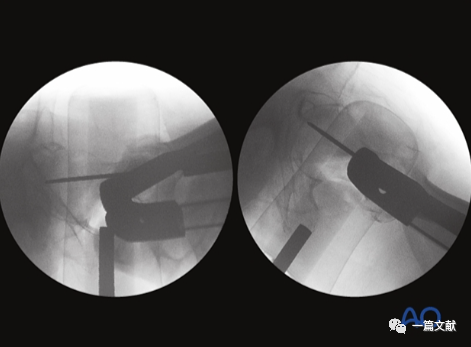

侧位片主要用来判断骨折复位情况及前倾角。但是,侧位片不是判断内固定位置的最佳选择,如下图:

左侧正位片显示颈干角,右侧侧位片显示前倾角。

只有如下图右侧的轴位片图像才能判断内固定在头颈骨块中的位置(左侧为侧位片)

同一患者的侧位像与轴位像的内固定透视图像如下图: